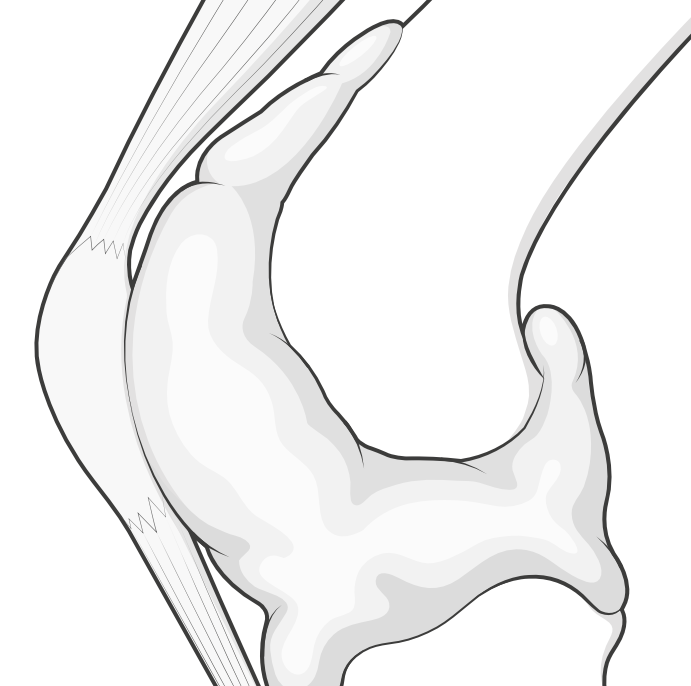

Illustration depicting the capsule swollen and distended. It would normally be deflated like a popped balloon.